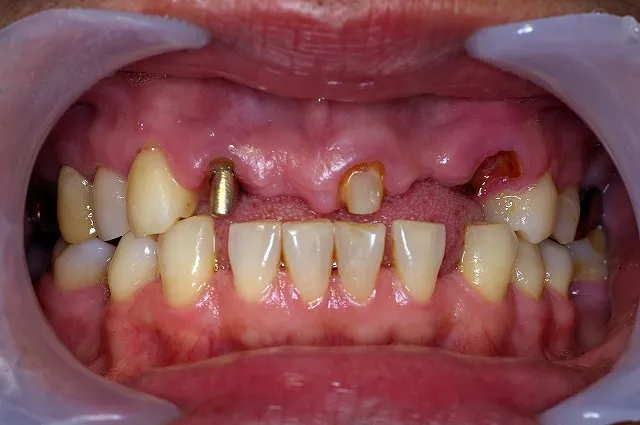

症例2

上顎:インプラントに磁性アタッチメントを装着し、総義歯装着

右上567、左上45インプラント+磁性アタッチメント

右下46、左下46:インプラント+セラミックメタルボンドブリッジ

右下321、左下13:セラミックメタルボンドクラウン